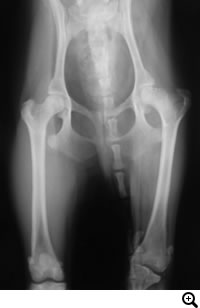

股関節形成不全症

股関節形成不全症とは

成長過程で股関節(寛骨と大腿骨)の発育異常が生じ、股関節に緩みが引き起こされる疾患です。緩みのある不安定な股関節を動かすことで、関節の軟骨部分が損傷を受け関節炎がはじまります。関節炎による痛みから跛行を呈します。

触診、レントゲン検査

• THR(Total Hip Replacement)/ 股関節全置換術

Micro THR(Micro Total Hip Replacement)/ 小型犬・猫用股関節全置換術

• DPO(Double Pelvic Osteotomy)/ 二点骨盤骨切り術

TPO(Triple Pelvic Osteotomy)/ 三点骨盤骨切り術

• FHO(Femoral Head Osteotomy)/ 骨頭切除術

• JPS(Juvenile Pubic Symphysiodesis)/ 若齢期恥骨結合固定術

全股関節置換術は股関節形成不全やその他の股関節の異常(レッグペルテス、骨頭骨折等)に対して行われる根治的治療法で、機能の回復に関しては現在のところ最もすぐれた治療法です。機能しない、あるいは痛みを持つ股関節をチタンの人工関節に取り替える方法です。6カ月齢からあらゆる年齢で可能な手術です。

5カ月齢~8カ月齢までの症例で有効な手術。腸骨・恥骨の二点もしくは腸骨・恥骨・坐骨の三点に骨切りをおこない、寛骨臼による大腿骨頭のカバーがよくなるよう腸骨を外側へ回転させる術式です

大腿骨頭を切除することで、寛骨臼と軟骨が損傷した大腿骨頭の直接的な接触をなくし痛みを取り除く方法です。何らかの原因でその他THR・DPO・TPOの手術ができない場合、保存的療法に反応しない場合、救済的な手術としておこないます。骨頭を切除した関節周囲に線維性偽関節が形成されるまで、不安定になるため、患肢を着地し負重するようになるまである程度の期間を要します。歩様が改善されるまで、リハビリテーションを行いながらサポートをいたします。

股関節形成不全を発症する可能性がある幼弱犬におこなう予防的な手術。

12~18週齢で可能な手術。恥骨結合を電気的に焼灼することで骨の成長を停止させます。これにより、寛骨臼による大腿骨頭のカバーがよくなるよう骨盤の形状を変化することを期待して行う手術です。